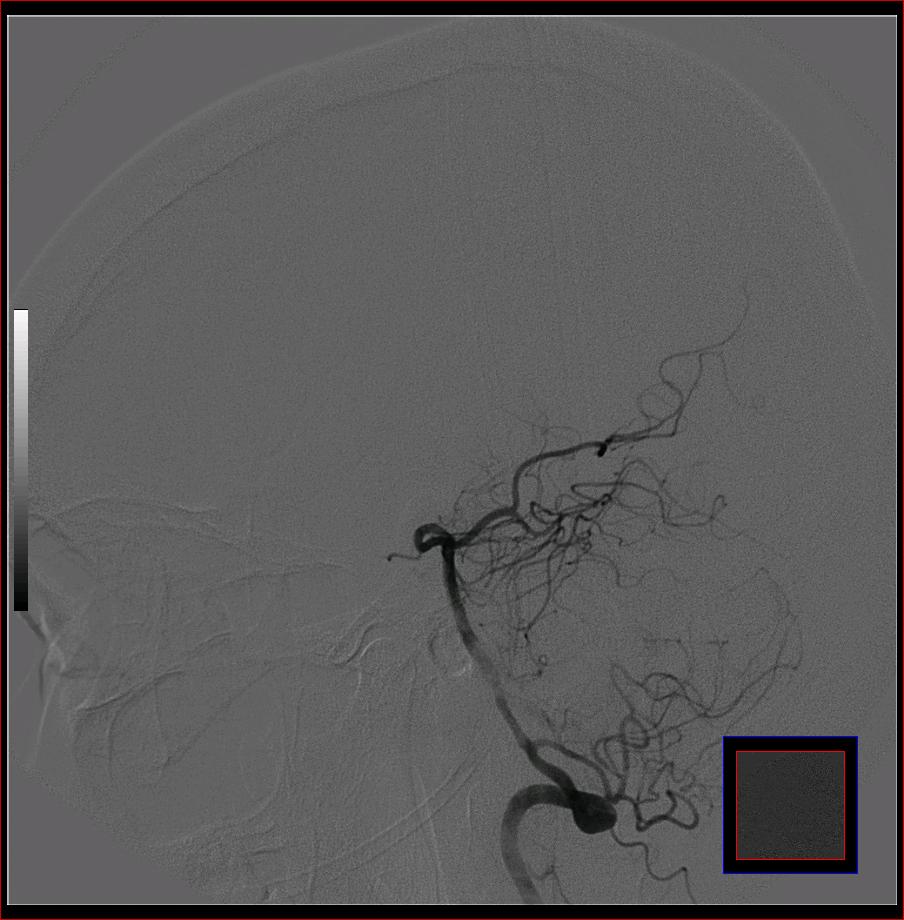

标题: DSA0121:脑血管造影

男,65岁,肢体无力。

右侧大脑前a缺如.左侧大脑中动脉m1段狭窄,远端分支分布稀疏.

前交通或稍远端动脉瘤要仔细查,左大脑中动脉狭窄要鉴别,有可能是痉挛,因为造影导管插得稍深啦。其它就是供血动脉变异较大

烟雾病